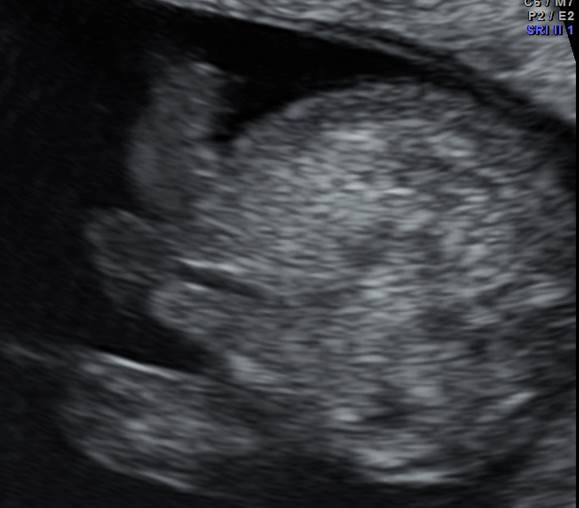

Вопрос 2

КТР 50 мм. Что видим? Что порекомендуем?